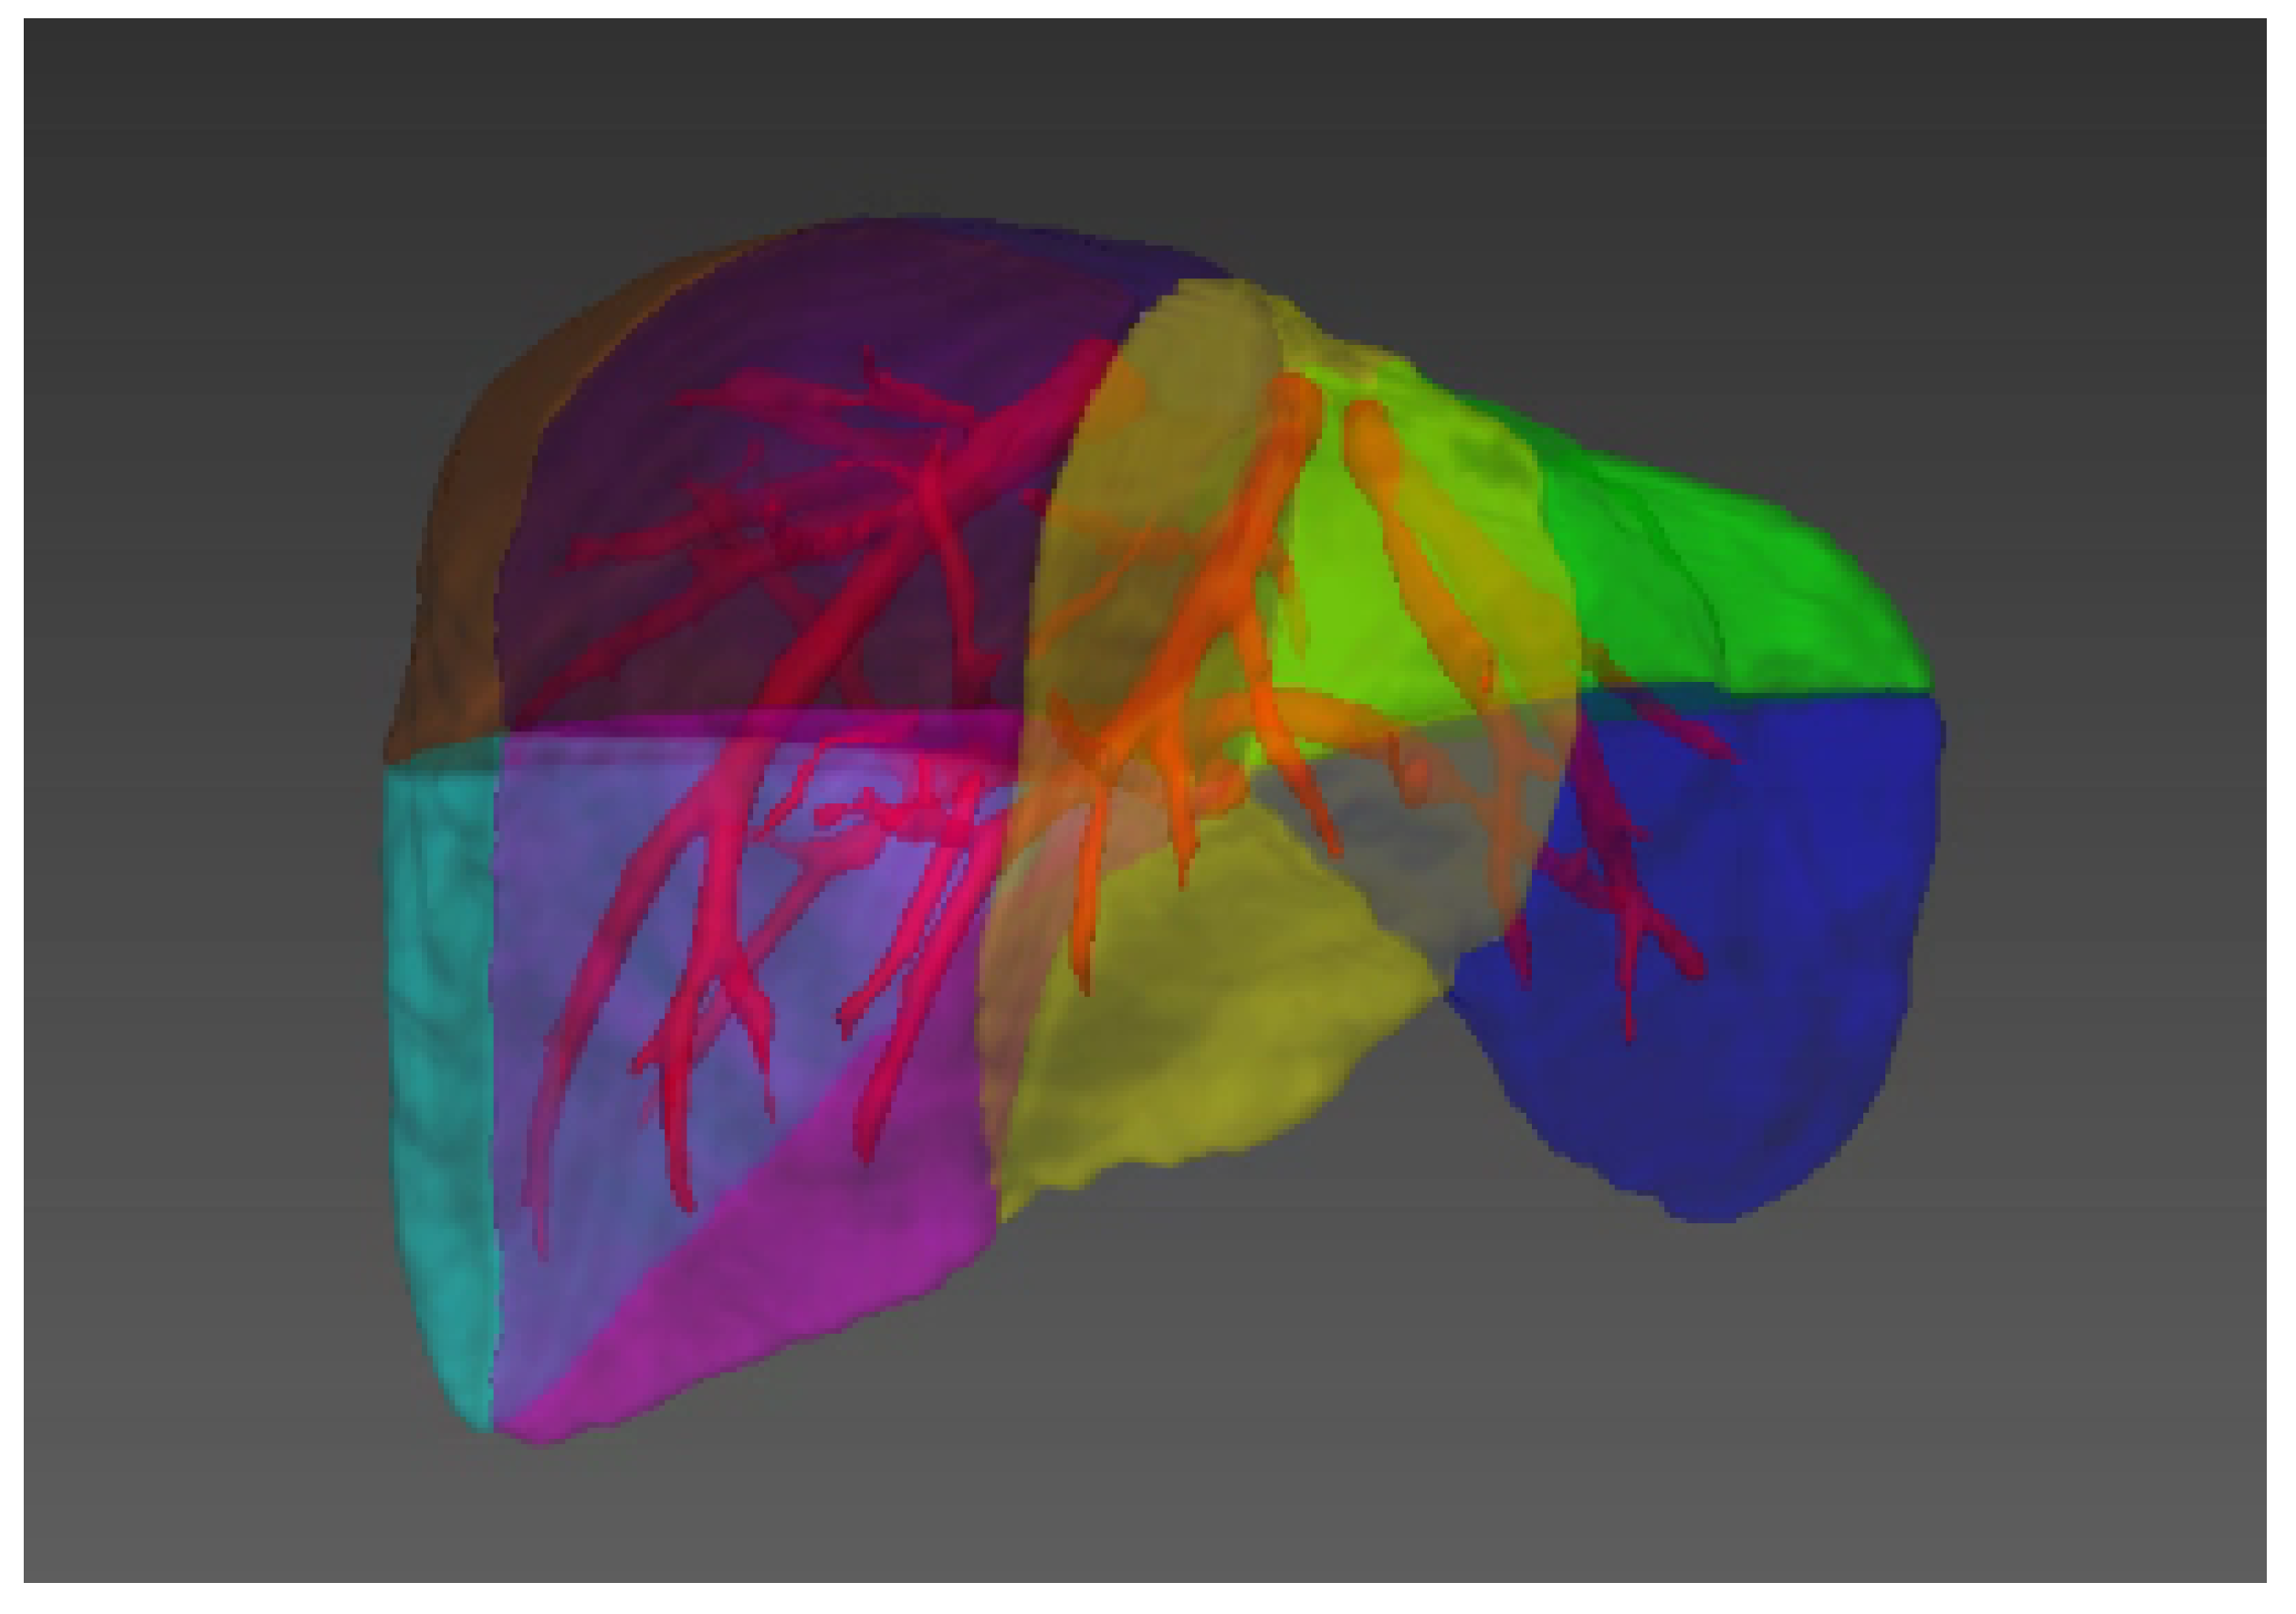

- Chen, Y.; Yue, X.; Zhong, C.; Wang, G. Functional region annotation of liver CT image based on vascular tree. BioMed Res. Int. 2016, 2016, 5428737. [Google Scholar] [CrossRef] [PubMed] [Green Version]

- Pan, J.; Zhang, J.; Luo, S.; Zhang, J.; Liang, Y. Automatic annotation of liver computed tomography images based on a vessel-skeletonization method. Int. J. Imaging Syst. Technol. 2020, 30, 704–715. [Google Scholar] [CrossRef]